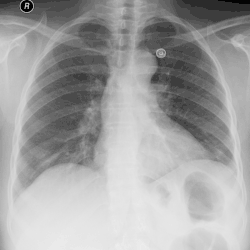

Atelectasis

Chest x-ray demonstrating severe atelectasis or collapse of the right lung and mediastinal shift towards the right.

Atelectasis is the partial collapse of a lung that is reversible. There are numerous etiologies, including post-operative atelectasis, surfactant deficiency, mucus plugging, and foreign body aspiration. Notably, post-operative atelectasis is thought to be caused by general anesthesia administration. Collapse of the affected lung shifts mediastinal structure towards the same side and can be observed on chest x-ray or CT. Radiographic features include increased opacification of collapsed lung and/or tracheal shift.[14]